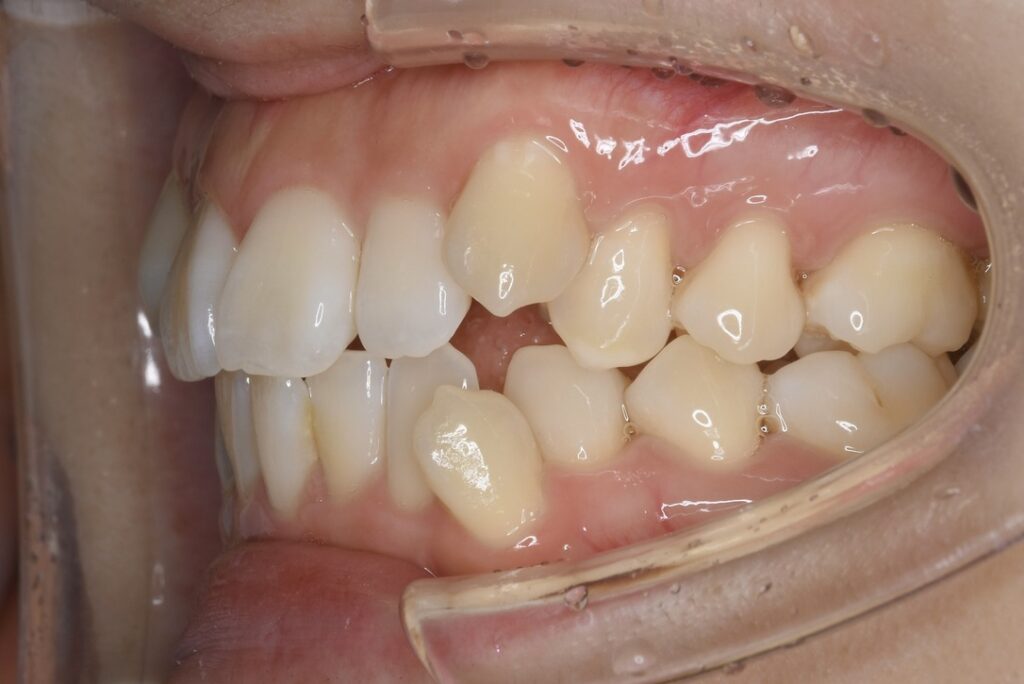

| 主訴 | 写真を見て歯並びが気になる。特に下の前歯はガタガタが強く治したい。 |

|---|---|

| 診断名・主な症状 | 叢生 |

| 年齢 | 19歳 |

| 治療内容 | 上下とも歯並びの幅を広げることでできたスペースを利用して、ガタガタを解消しました。 |

| 使用装置 | 表側矯正(ワイヤー) 矯正用ミニインプラント |

| 抜歯部位 | 抜歯なし |

| 治療期間 | 1年10ヶ月 |

| 通院回数 | 25回 |

| 費用 | 91万円程度(税別) 220 |

| リスク・副作用 | 痛み、歯肉退縮、歯根吸収、抜歯に伴う出血や腫れが生じることがあります。 |